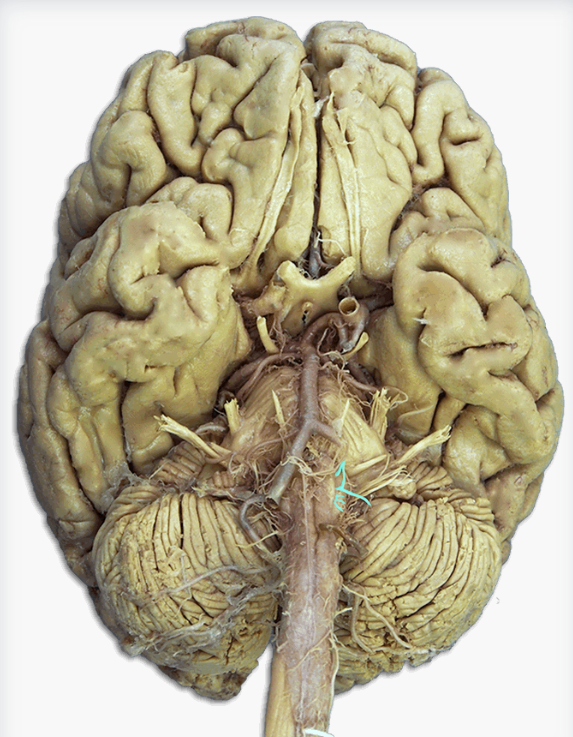

Labeling Neuroanatomy

Extensive diagrams and images of brain regions, arteries, and nerves. Made as a study guide for the neuroanatomy exam in Behavioral Neurobiology (PSYCH 384).

What is this?

Anterior cerebral artery

Label this structure

Hypoglossal (CN XII) nerve

Label this cerebral artery

Basilar artery

Label this cerebral artery

Anterior communicating artery

Label this cerebral artery

Middle Cerebral Artery

Label this cerebral artery

Posterior Cerebral Artery

Name this brain structure

Temporal lobe

Label this cranial nerve

Olfactory (CN I) nerve

Label this cranial nerve

Optic (CN II) nerve

Label this cranial nerve

Oculomotor (CN III) nerve

Label this cranial nerve

Trochlear (CN IV) nerve

Label this cranial nerve

Trigeminal (CN V) nerve

Label this cranial nerve

Abducens (CN VI) nerve

Label this cranial nerve

Facial (CN VII) nerve

Label this cranial nerve

Vestibulocochlear (VIII) nerve

Label this cranial nerve

Glossopharyngeal (CN IX) nerve

Label this cranial nerve

Vagus (CN X) nerve

Label this cranial nerve

Accessory (CN XI) nerve

Label this cranial nerve

Hypoglossal (CN XII) nerve